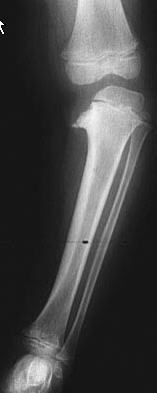

Femur fracture treatment by age

< 6 mo

7 mo - 5 yo

6 - 11 yo

12 and up (approaching maturity)